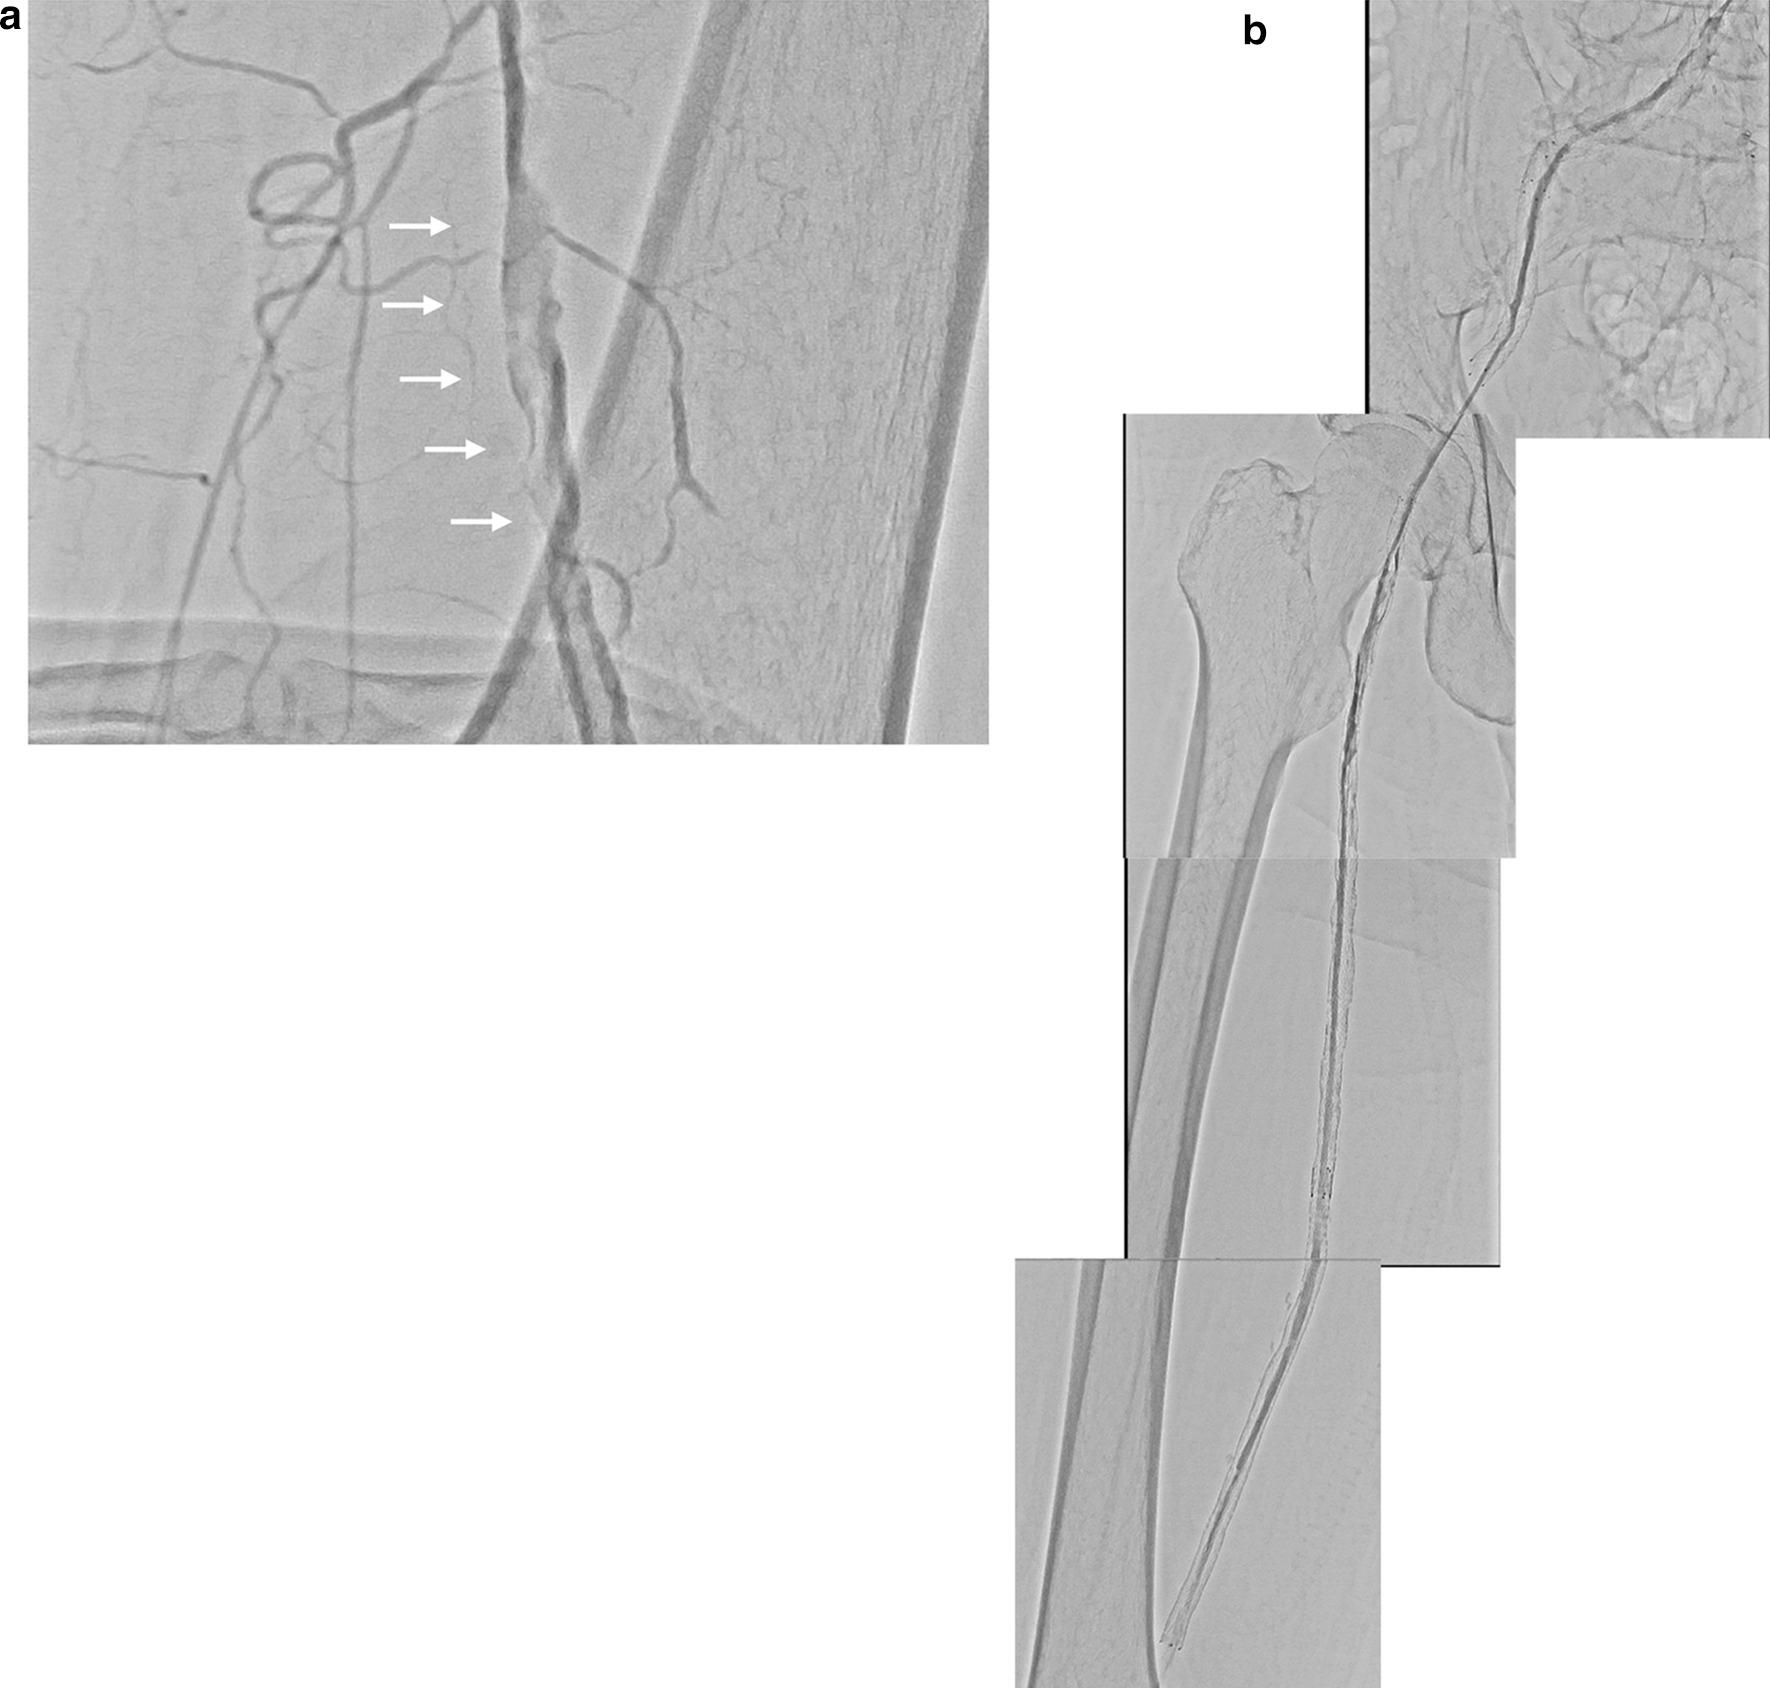

A 72-year-old Japanese man was admitted with acute limb ischemia due to failed aortofemoral and femoropopliteal bypass grafts. Endovascular treatment with balloon angioplasty, thrombectomy, and stent implantation in the long chronic total occlusion from the right common iliac artery to the superficial femoral artery did not result in efficient flow due to thrombus transfer from a failed aortofemoral bypass graft. However, a rescue femorofemoral bypass (the left femoral to the right deep femoral artery) improved his symptoms, and implanted in-stent flow was gradually recovered. Lower extremity angiography performed 5 months later confirmed the patency of the iliofemoral in-stent flow. However, the femorofemoral bypass graft was unfortunately occluded due to the progression of left external iliac artery stenosis. The patency of the iliofemoral in-stent flow was confirmed at 1 year by ultrasonography.

一名72岁的日本男性因主-股动脉和股-腘动脉旁路移植失败导致急性肢体缺血入院。对从右髂总动脉至股浅动脉的长段慢性完全闭塞病变进行球囊血管成形术、血栓切除术和支架植入的血管腔内治疗,因主-股动脉旁路移植失败导致的血栓转移,未能实现有效血流。然而,一次抢救性股-股动脉旁路移植术(从左股动脉至右股深动脉)改善了他的症状,支架内植入后的血流逐渐恢复。5个月后进行的下肢血管造影证实了髂股动脉支架内血流的通畅。然而,不幸的是,由于左髂外动脉狭窄进展,股-股动脉旁路移植血管闭塞。1年后通过超声检查证实了髂股动脉支架内血流的通畅。